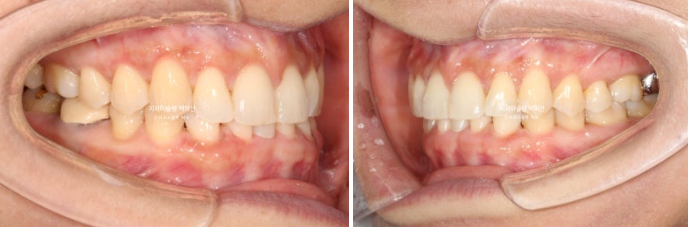

이제 전 후 비교 보겠습니다

총 치료기간은 1년, 재제작은 1회 했고 교정치료 내원간격은 5개월 입니다.

24.08~25.08

쓰러져 있던 두번째 큰어금니는 잘 세웠습니다.